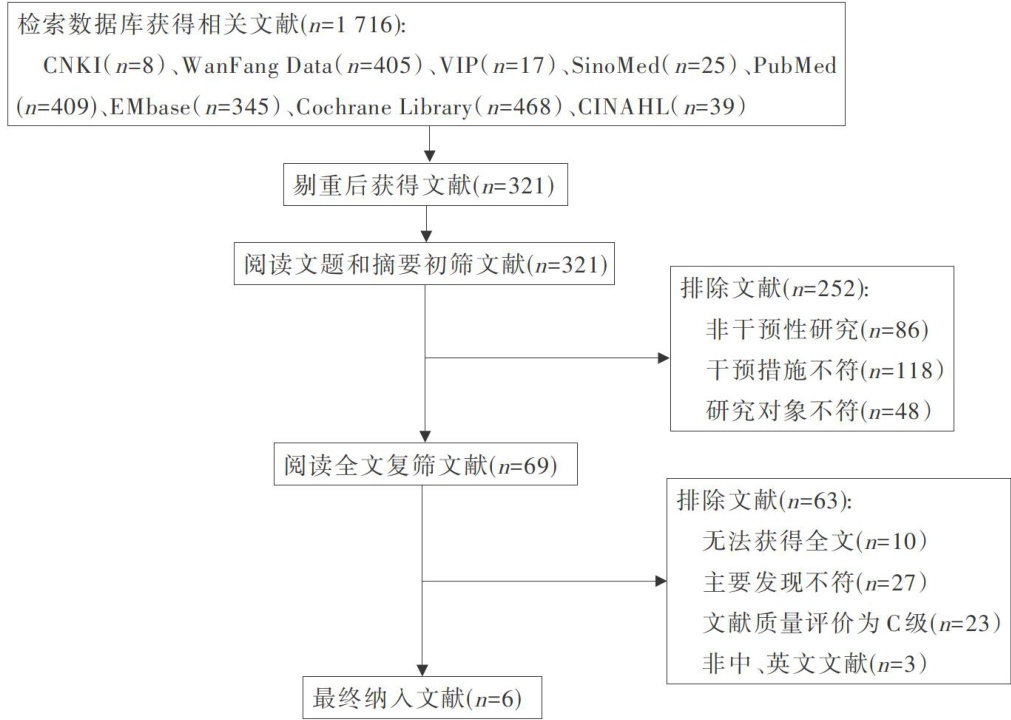

科研论著 | 腹腔镜手术病人术中非计划性低体温预防与管理的最佳证据总结

科研论著 | 腹腔镜手术病人术中非计划性低体温预防与管理的最佳证据总结